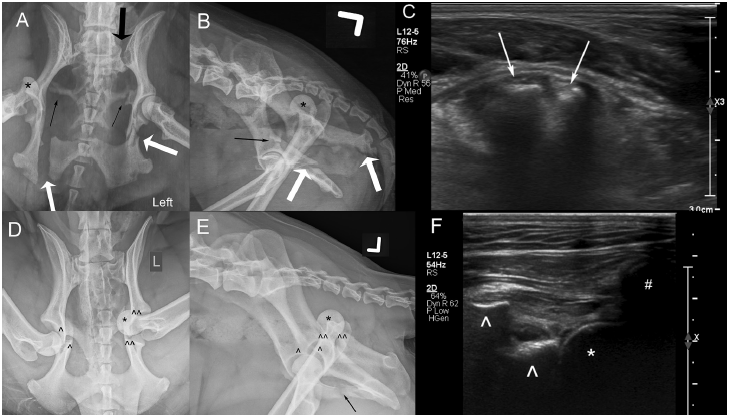

CSCU Assisted Pub: Ultrasound is an accurate imaging modality for diagnosing hip luxation in dogs presenting with hind limb lameness doi.org/10.2460/javma.… Congratulations! @CornellRsrch @cornellvet